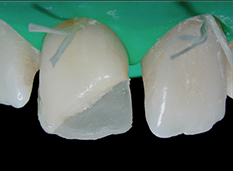

Avec l’intervention de Gautier Weisrock sur la restauration composite antérieure, on sera pleinement au coeur de la question esthétique. Il donnera les clés au praticien sur les deux points fondamentaux de cette problématique : la couleur et la forme. Il éclairera le praticien dans le choix de la teinte et sur les autres paramètres influençant les résultats esthétiques (forme de préparation, polissage, etc.).